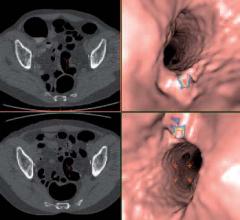

Computer-aided detection (CAD) software constitutes a set of algorithms which, using a pattern-recognition technique, aids the radiologist in detecting potentially diseased regions and lesions. It uses clinical images obtained from various imaging modalities. CAD has long since left behind its branding as a mammography tool and has now widened its application areas, becoming a valuable tool for detection and diagnosis in cardiology.

Historically, advanced visualization systems have been rigid, “one size fits all” products. However, recent developments have enabled fully customizable protocols and user interfaces, ensuring the system adapts to each user’s workflow.

Several trends in advanced visualization software were highlighted at the 2010 Radiological Society of North America (RSNA) meeting. The biggest advance was software to create a video loop of a dynamic 3-D dataset from computed tomography (CT) or magnetic resonance imaging (MRI) to show life-like anatomical function. Other trends included software now being accessible on the Internet via thin-client computers, compatibility with the iPad and smart phones, and the addition of more advanced software to enhance images and automate workflow and measurements.